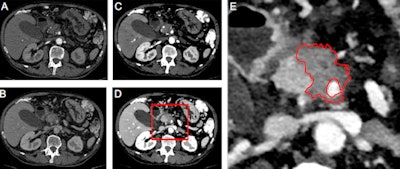

Conventional clinical CT diagnosis uses 70-kiloelectron-volt (keV) x-ray tubes to generate images. It gives a very clear picture of anatomical structures, but has a limited ability to distinguish between tissues with similar x-ray properties. Dual-energy CT resolves this by using two different voltages, explained Dr. Fabian Lohöfer, a radiologist at the TUM, during the German Radiology Congress (Deutscher Röntgenkongress, RöKo 2017).

Dual-source CT is a clinically widespread dual-energy procedure that replaces a single tube with two: one of 70 and the other of 40 keV. Dual-layer spectral CT, on the other hand, uses one tube but two detectors in series.

Another advantage of dual-layer spectral CT is that it gives a clearer visual picture of tumors, with a clear distinction between tumor and healthy tissue, and of blood-vessel involvement, which is critically important in preoperative planning. It's particularly good at defining smaller tumors, he elaborated. The technology benefits not only surgeons in carrying out operations, but also physicians who want to use CT to establish whether a specific therapy will work.